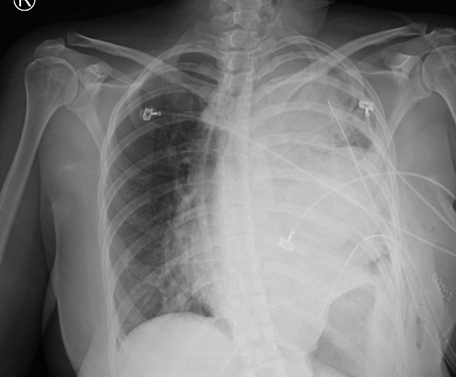

The patient underwent emergent chest tube placement with thoracoscopy. Adhesions were found seeding the right thoracic cage and adhering to the collapsed lung. Biopsy and lysis of adhesions allowed for lung re-expansion. Thoracoscopy allowed for drainage of 3700 mL of serosanguinous fluid under pressure from the left thorax, with an additional 220 mL drained in the hours following the surgery. Chest radiograph was obtained immediately after chest tube placement (Figure 3) to verify the positioning and severity of mediastinal shift and repeated on postoperative day (POD) 1. Computed tomography imaging on POD 4 revealed an increase in the mass’s size measuring 14.3 × 11.5 × 15.7 cm (Figure 4). Imaging also revealed a persistent but decreased mediastinal shift to the right with a hydrothorax. During the patient’s one-month admission, total drainage from the chest tubes totaled 15.929 liters of serosanguinous fluid.

Figure 4: CT imaging of the chest on post-operative day (POD) 4 revealed subsegmental pulmonary emboli involving all lobes of the right lung with no evidence for heart strain. Improved aeration of left lung is seen. Large mediastinal mass now measuring approximately 14.3 × 11.5 × 15.7 cm noted occupying much of the left hemithorax with resultant mediastinal shift right from mass effect. Two surgical chest tubes are in place with left-sided hydropneumothorax.